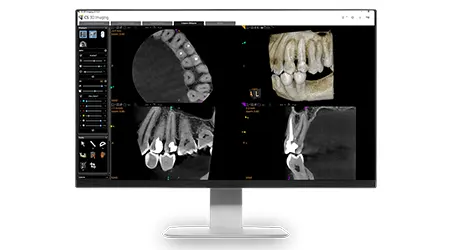

Carestream CS 8200 3D Access Edition

At our practice, we focus on technologically supported care, not just aesthetics. Using the CS 8200 3D system, we can:

• Diagnose issues hidden from your usual exam and X-rays

• Plan treatments (implants, root canals, orthodontics) with more precision

• Minimize radiation exposure while improving image clarity

• Perform more in-house work, reducing referral delays